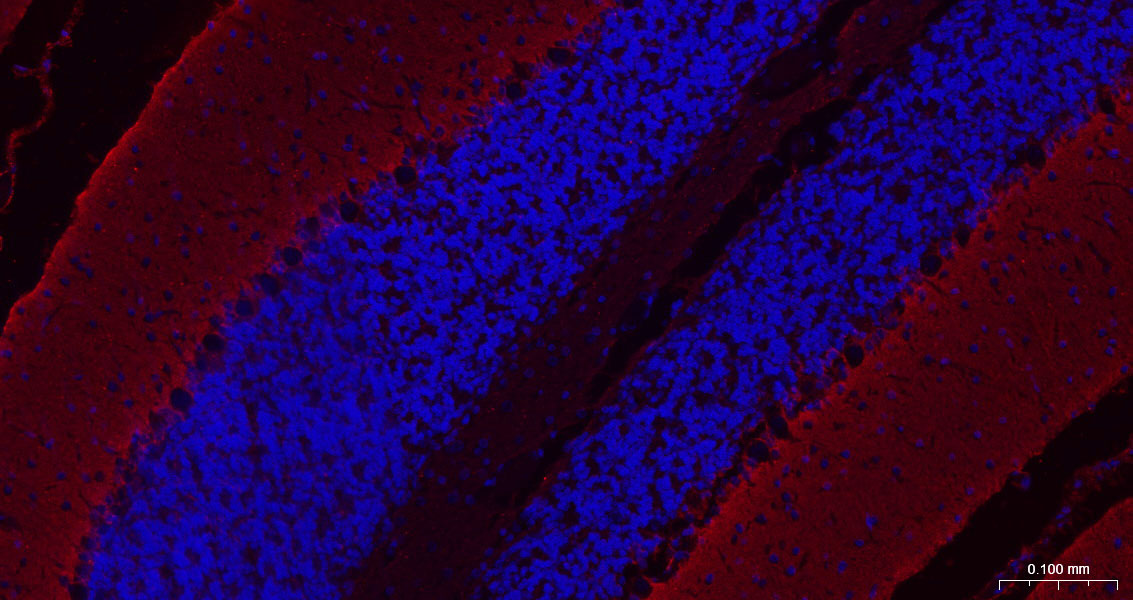

Paraformaldehyde-fixed, paraffin embedded Rat Cerebellum; Antigen retrieval by boiling in sodium citrate buffer (pH6.0) for 15 min; The section was incubated with EAAT1 Monoclonal Antibody, Unconjugated (bsm-60880R) at 1:200 overnight at 4°C. Followed by conjugated Goat Anti-Rabbit IgG antibody (Red, bs-0295G-BF594), DAPI (blue, C02-04002) was used to stain the cell nuclei.